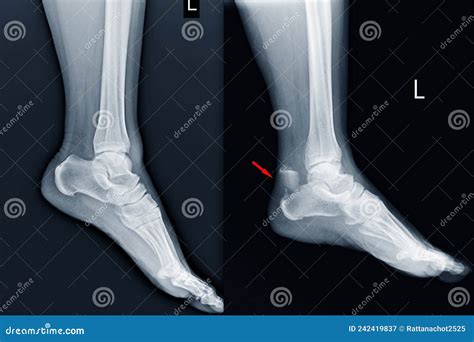

Interpreting the results of a Calcaneus X Ray requires the expertise of a radiologist or orthopedic specialist. The images are carefully examined for signs of fractures, dislocations, or other abnormalities. Here are some common findings that may be identified:

• Fractures: These can range from simple cracks to complex fractures involving multiple bone fragments. The location and severity of the fracture will determine the appropriate treatment.

• Dislocations: These occur when the bones in the heel area are displaced from their normal position. Dislocations can cause significant pain and may require surgical intervention.

• Bone Spurs: These are bony projections that can form on the heel bone due to chronic stress or inflammation. Bone spurs can cause pain and discomfort, especially during weight-bearing activities.

• Achilles Tendon Injuries: While not directly visible on a Calcaneus X Ray, the presence of a calcaneal spur or other bony abnormalities can indicate underlying issues with the Achilles tendon.

• Plantar Fasciitis: This condition involves inflammation of the plantar fascia, a thick band of tissue that runs along the bottom of the foot. While not directly visible on an X-ray, a Calcaneus X Ray can help rule out other causes of heel pain.

• Heel Spurs: These are bony projections that can form on the underside of the heel bone. They are often associated with plantar fasciitis and can cause significant pain and discomfort.